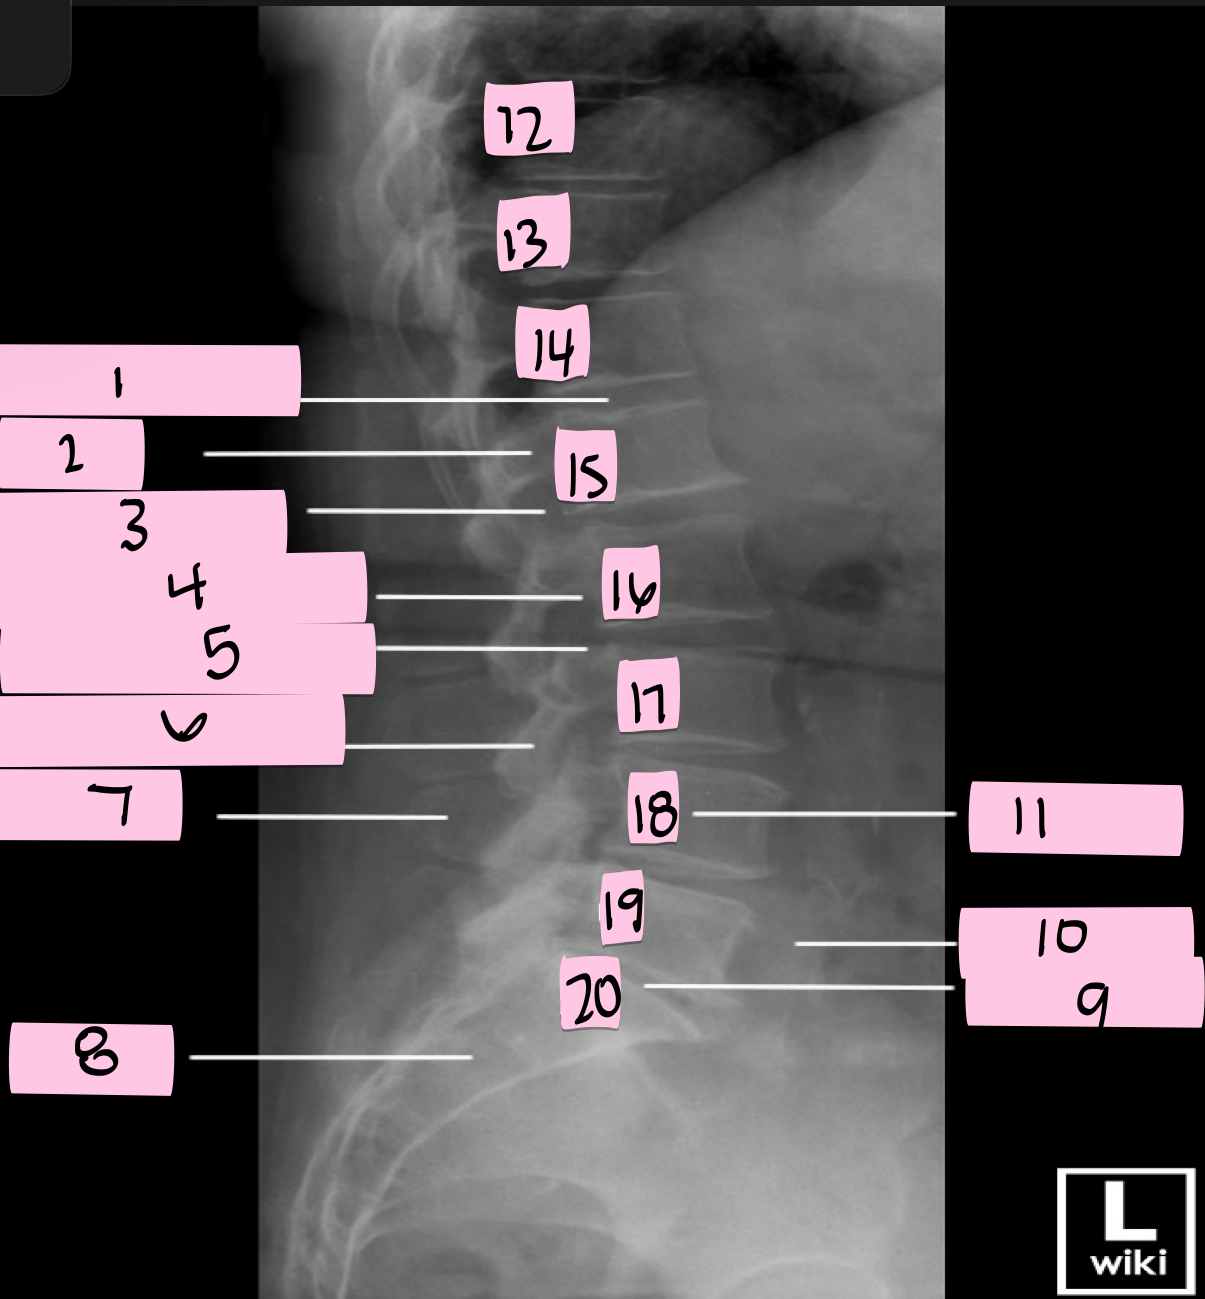

What is 1 pointing to?

Intervertebral disk

What is 2 pointing to?

Pedicle

What is 3 pointing to?

Intervertebral foramen

What is 4 pointing to?

Inferior vertebral notch

What is 5 pointing to?

Superior vertebral notch

What is 6 pointing to?

Inferior articular process

What is 7 pointing to?

Spinous process

What is 8 pointing to?

Sacrum

What is 9 pointing to?

L5 S1 joint

What is 10 pointing to?

Iliac crest

What is 11 pointing to?

Vertebral body (L4)

What is 12 pointing to?

T10

What is 13 pointing to?

T11

What is 14 pointing to?

T12

What is 15 pointing to?

L1

What is 16 pointing to?

L2

What is 17 pointing to?

L3

What is 18 pointing to?

L4

What is 19 pointing to?

L5

What is 20 pointing to?

S1